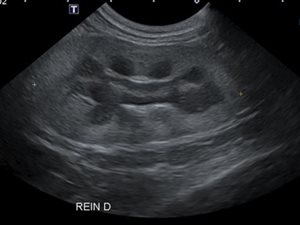

- L’échographie: abdominale, thoracique, superficielle…